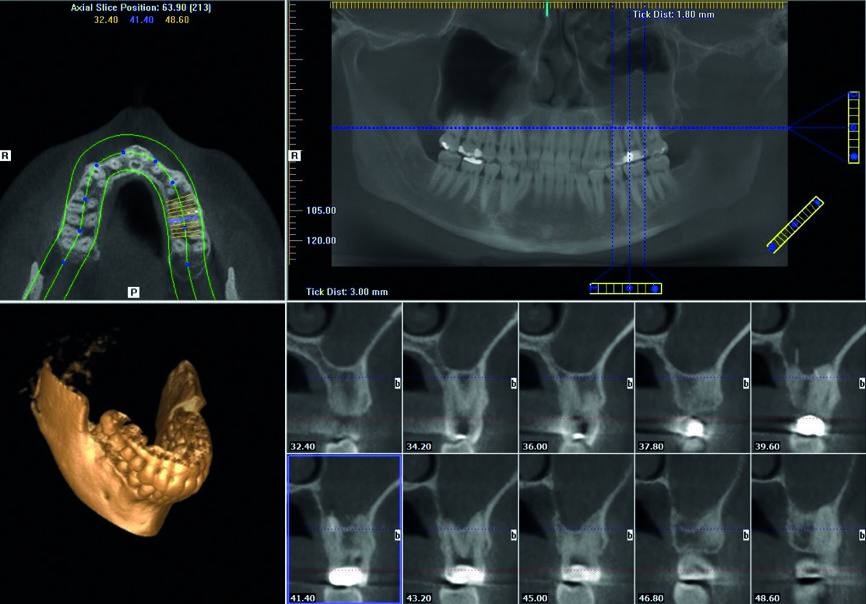

Un patient avait été adressé au cabinet en raison de problèmes associés à la fracture d’une lime. Il était pilote de ligne et se plaignait d’écoulements nasaux purulents lorsqu’il était en vol. La radiographie pré-opératoire (Fig. 1) a distinctement montré la présence de deux fragments d’une lime fracturée dans les canaux mésiaux et d’un cône traversant l’apex de la racine palatine. Après l’imagerie CBCT avec iCAT, il est apparu clairement que le sinus gauche était presque totalement rempli de liquide inflammatoire (Fig. 2) et que le cône présent dans le canal palatin pénétrait dans le sinus. Sur l’image de reconstruction multi planaire (MPR), nous pouvions également distinguer les deux fragments de lime fracturée dans les deux canaux mésiaux (Figs. 3 et 4) et aussi un autre fragment dans le sinus sans aucun contact avec le canal (Fig. 5). L’utilisation de différents filtres nous a permis de visualiser les fragments de lime (Figs. 6–9), ainsi que l’inflammation et le fragment de lime fracturée à l’intérieur du sinus. Nous avons également mieux perçu la position du cône qui émergeait du canal palatin et pénétrait dans le sinus.

Le plan de traitement a consisté à tenter de résoudre le problème par une approche classique et, au besoin, par une microchirurgie, en vue de conserver la dent. J’ai pu retirer le cône de la racine palatine a l’aide de limes H (Hedstrom) mais il était impossible de contourner les fragments de lime présents dans la racine mésiale, ou même de les atteindre avec des inserts ultrasoniques. Je me suis résolu à ne pas en faire trop afin de ne pas créer un nouveau problème, tel qu’une perforation de la paroi canalaire, et j’ai décidé de sceller les canaux (Fig. 10). La décision de traiter les canaux mésiaux par une approche chirurgicale a été prise immédiatement. J’ai sectionné 3 mm de la racine mésiale à l’aide d’une pièce à main Impact Air (SybronEndo), ce qui m’a donné une vue directe sur la membrane de Schneider, de laquelle le troisième fragment dépassait à peine (Figs. 11 et12). Je suis parvenu a le saisir délicatement et à l’extraire (Fig. 13). La figure 14 montre la situation post-opératoire, après la fin de la préparation à retro des canaux mésiaux.